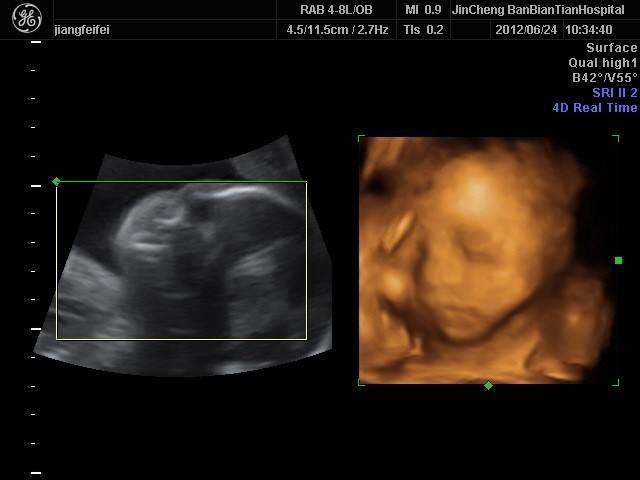

四维彩超是目前比较流行的孕检之一,四维能对胎儿头面部立体成像,可清晰显示胎儿的状态,网上很多四维是女孩但是却生了男孩的案例,那么四维女孩翻盘几率大吗?

四维一般都是二十四周以后照的,这么大的孕周出错的机会还是比较小的,虽然不是百分之百准确的,但是出错的概率还是会比较少的,大部分情况都是不会出现翻盘的情况,四维超声同其它超声检查相比,可以实时观察人体内部器官的动态运动,也能准确地分辨出胎儿的性别。虽然四维彩超能够看清胎儿的性别,但在检查过程中,为了避免透露胎儿的性别,医生会主动的回避胎儿的性别特征以及下半身,因此最好找熟人的医生做这样才能更准确知道宝宝的性别。